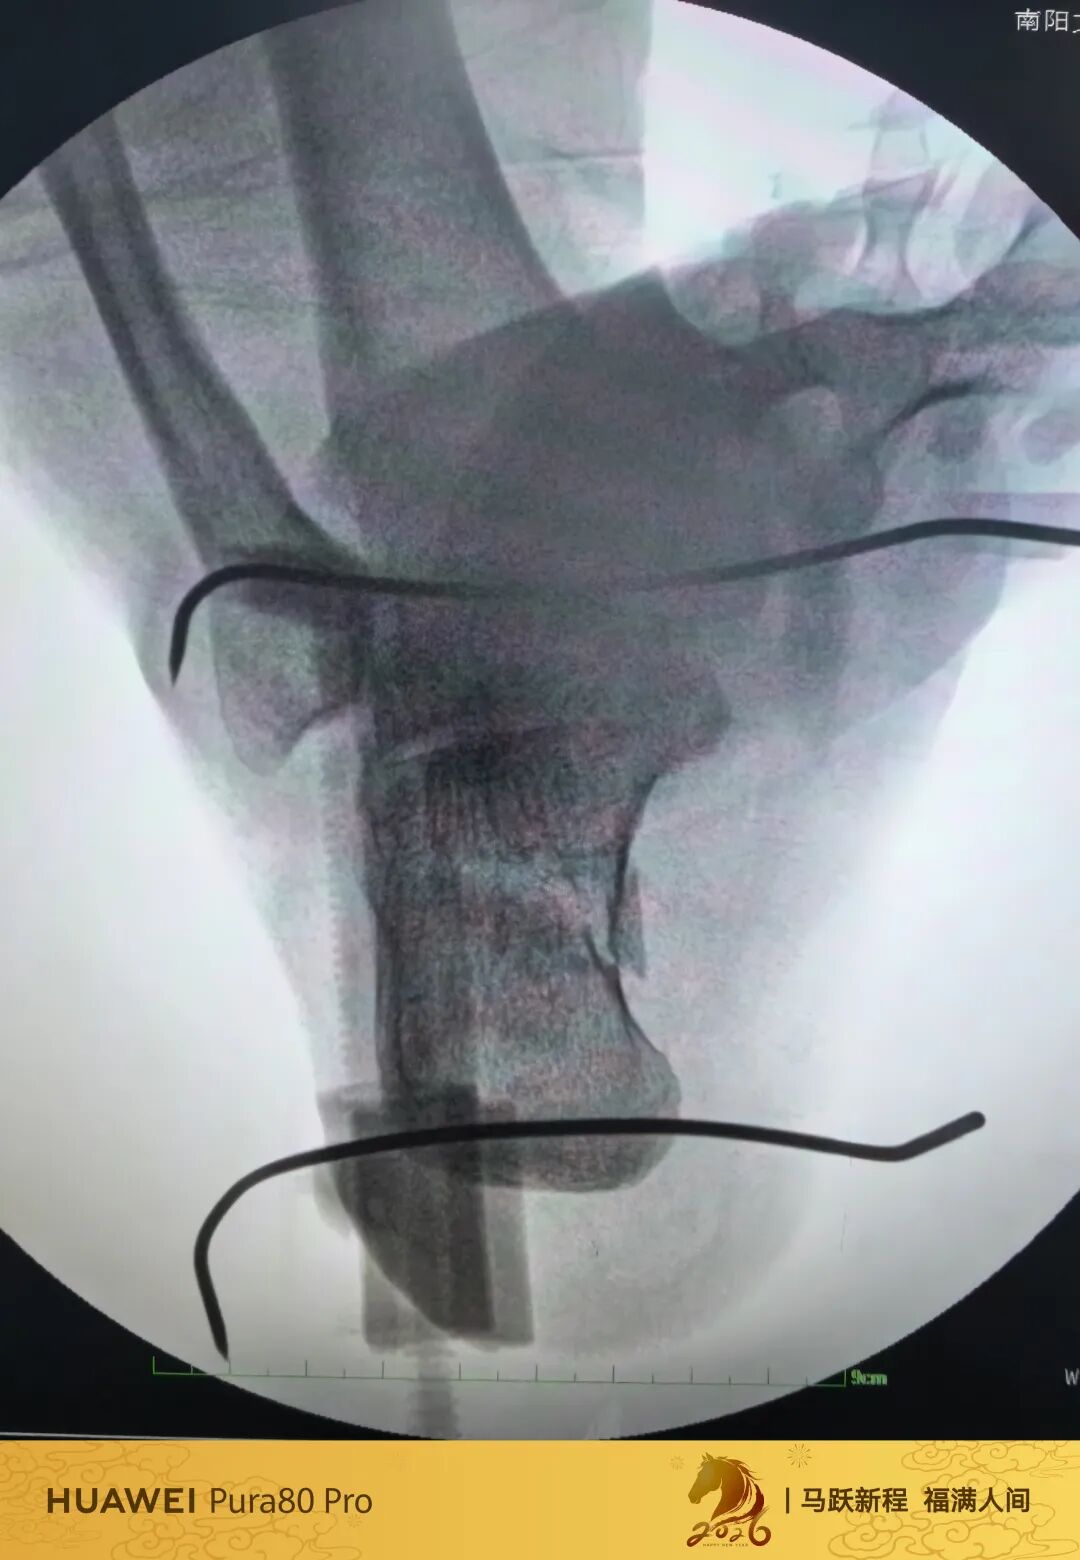

第60例跟骨微创了,虽然已经彻底放手,尽量只动嘴,但还是有小问题小瑕疵,无法完全避免。